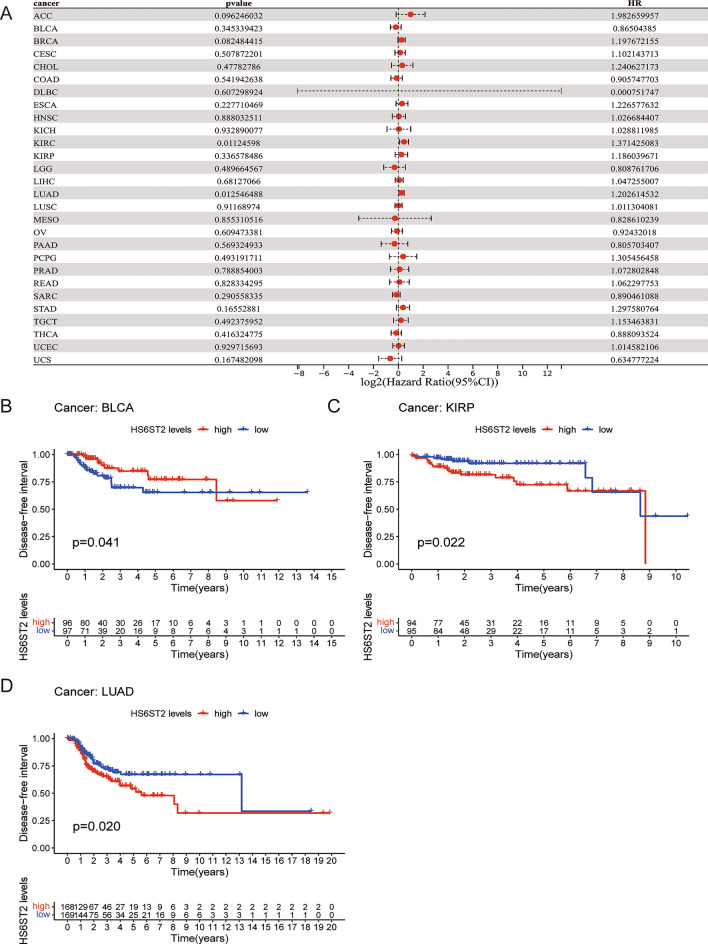

Via the TCGA database, we examined the value of HS6ST2 mRNA expression for predicting OS, DFI, DSS, and PFI across cancers. Cox regression analysis revealed that low HS6ST2 expression was connected with poorer OS in breast invasive carcinoma, mesothelioma, kidney renal clear cell carcinoma, uveal melanoma, and adrenocortical carcinoma but associated with better OS in rectum adenocarcinoma and bladder urothelial carcinoma (Fig. 3A). As determined by KM OS analysis, HS6ST2 was a protective factor for patients with bladder urothelial carcinoma and rectum adenocarcinoma but a risk factor for patients with kidney renal papillary cell carcinoma and uveal melanoma (Fig. 3B–E). We also determined the correlation between the expression of HS6ST2 and the DFS rate in 33 different cancers. HS6ST2 was found to be a protective factor in bladder urothelial carcinoma and a risk factor in kidney renal papillary cell carcinoma, stomach adenocarcinoma, adrenocortical carcinoma, and according to Cox regression analyses (Fig. 4A). Similarly, KM analysis of DSS uncovered that HS6ST2 was a risk factor in stomach adenocarcinoma, kidney renal papillary cell carcinoma, and uveal melanoma but acted as a protective factor in bladder urothelial carcinoma (Fig. 4B–E).

To evaluate the efficacy of radical surgery, the DFI was assessed, and this index was then used to predict the median time to recurrence. KM and Cox regression analyses showed that high HS6ST2 expression was associated with worse DFI in lung adenocarcinoma and kidney renal papillary cell carcinoma and with better DFI in bladder urothelial carcinoma (Fig. 5A–D). In addition, the correlation between PFI and HS6ST2 expression was examined to assess the responsiveness of cancers to palliative care. Cox regression analysis showed that HS6ST2 over-expression was associated with better PFI in pancreatic adenocarcinoma and thymoma but associated with poor PFI in uveal melanoma (Fig. 6A). According to the results of the KM analysis of PFI, HS6ST2 is a risk factor for patients with kidney renal clear cell carcinoma, kidney chromophobe, and uveal melanoma and a protective factor for bladder urothelial carcinoma, prostate adenocarcinoma, and thymoma (Fig. 6B–G). Our results demonstrated a significant correlation between HS6ST2 expression and outcomes in many types of cancer.